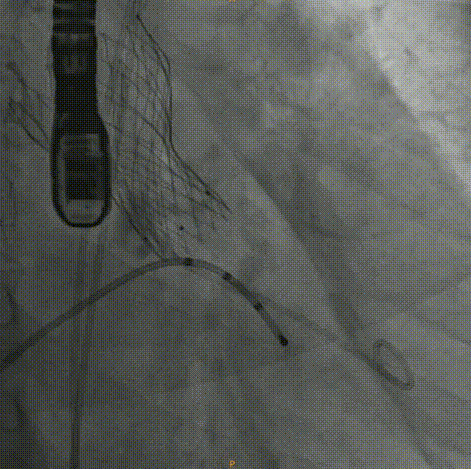

术中影像:

主动脉根部造影:左右冠灌注情况良好,瓣叶活动度一般,无明显反流。

20mm球囊预扩:冠脉灌注情况良好,瓣上结构改变,微量反流。

Venus26号瓣膜定位:结合瓣上结构考虑,采用0位释放。

Venus26号瓣膜释放:前三分之一慢放精准定位,中三分之一快放使瓣膜快速进入工作状态。

Venus26号瓣膜释放:位置良好,轻度反流,遂完全释放后采取后扩。

后扩后瓣膜最终形态。